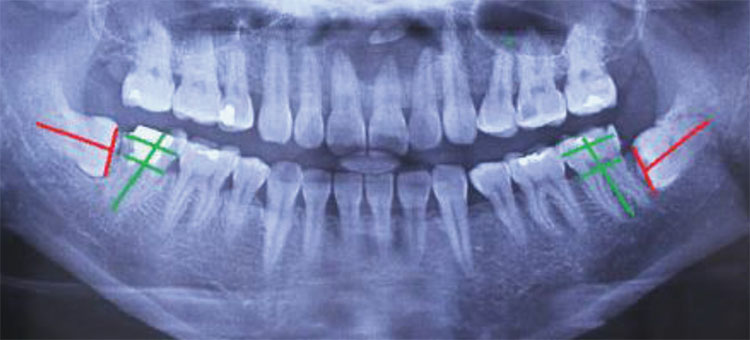

Trước khi đưa ra quyết định nhổ răng, bác sĩ sẽ tiến hành thăm khám tổng quát, chụp Xquang cho bệnh nhân để xác định hướng mọc của răng, phát hiện các vấn đề về răng miệng, bệnh lý như viêm lợi, viêm nướu, sâu răng hay viêm nha chu,…Nếu mắc các bệnh lý này thì cần điều trị dứt điểm các vấn đề này trước khi tiến hành nhổ răng khôn hàm dưới. Ngược lại, bạn có thể nhổ răng khôn hàm dưới bình thường nếu không có vấn đề gì.